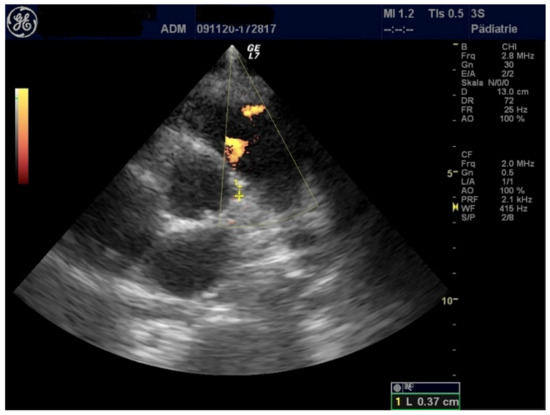

| LCA (mm) | 3.8 | 3.3 | 3.1 |

| RCA (mm) | 3.2 | 4.0 | 2.8 |

| Pericardial effusion (mm) | 7 | 3 | 5 |

| LVEF (%) | 81 | 69 | 73 |

| FS (%) | 50 | 39 | 41 |

| LCA (mm) | 3.7 | 3.2 | 2.8 |

| RCA (mm) | 3.3 | 3.0 | 2.4 |

| Pericardial effusion (mm) | 0 | 3–7 | <3 |